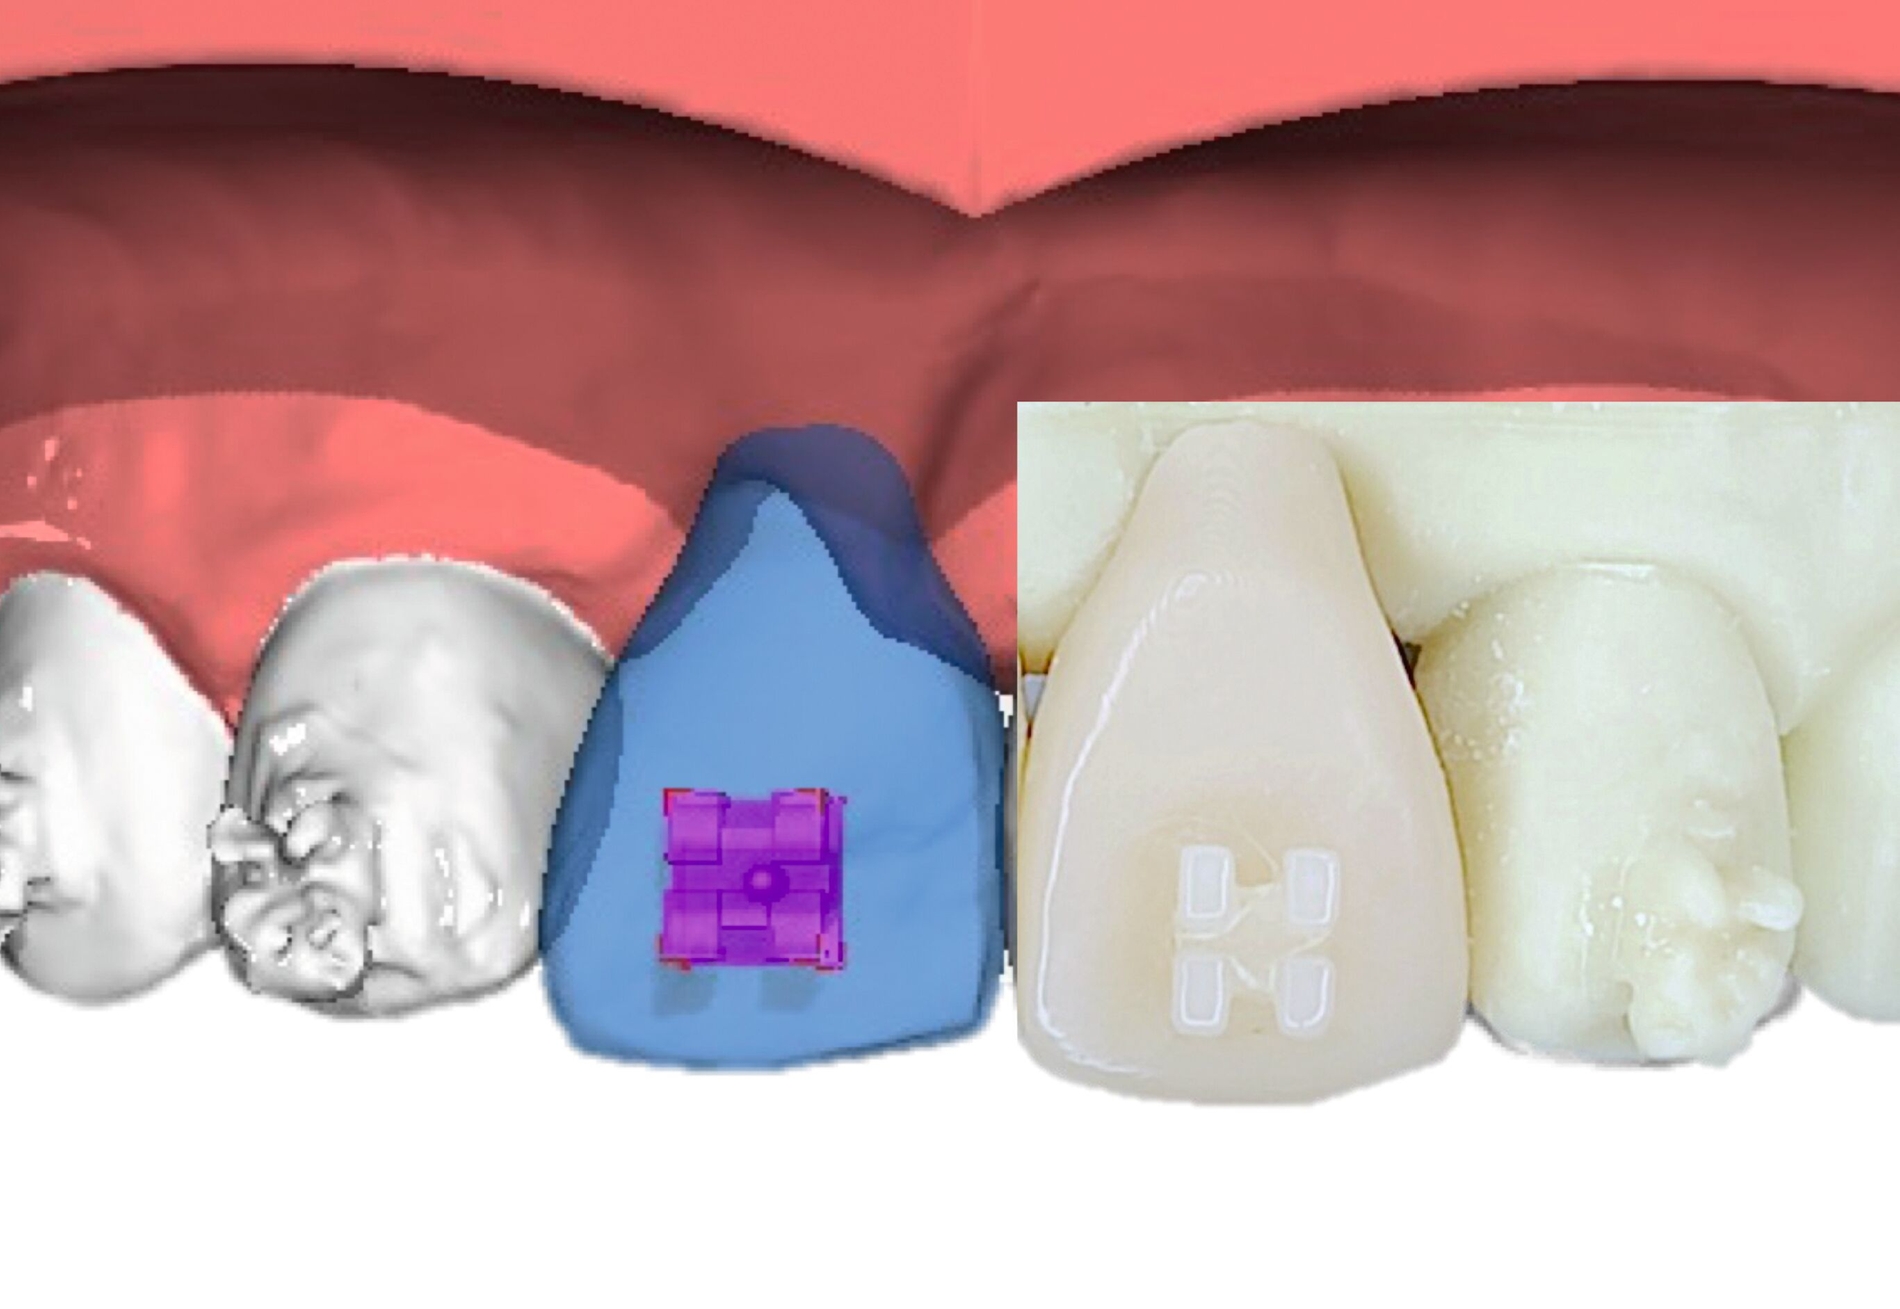

Als Alternative zu Alignern können auch Brackets mittlerweile im 3-D-Druckverfahren hergestellt werden [Sha et al., 2018; Sha et al., 2019; Bauer et al., 2023] (Abbildungen 2a und 2b). Neben der Nutzung des Angebots kommerzieller Anbieter (beispielsweise Lightforce Company) besteht dabei die Möglichkeit der Herstellung im praxisinternen 3-D-Drucker. Zum Einsatz eignen sich unter anderem Keramik-gefüllte 3-D-Druckkunststoffe der Biokompatibilitätsklasse IIa, die für einen langfristigen intraoralen Einsatz zertifiziert sind (zum Beispiel Permanent Crown Resin, Formlabs) [Papageorgiou et al., 2022; Bauer et al., 2023; Hodecker et al., 2023; Panayi, 2023].

Die Vorteile bestehen vordergründig in einem individualisierten Design, das die jeweiligen Therapieanforderungen berücksichtigt. Bisherige Forschungsarbeiten zeigen eine mit konventionellen Metallbrackets vergleichbare Präzision [Bauer et al., 2023], so dass eine korrekte Übertragung kieferorthopädischer Kräfte gewährleistet ist. Der Haftverbund zeigt sich gegenüber konventionellen Metallbrackets noch etwas schwächer [Hodecker et al., 2023]. Durch weitere Entwicklungen im Bereich der Bracketbasis dürfte diese Limitation jedoch adressiert werden können.

Auch die Herstellung zusätzlicher Elemente, wie beispielsweise Transpalatinalbögen aus Keramik-gefüllten 3-D-Druckkunststoffen, ist möglich (Abbildung 2c) [Thurzo et al., 2022], muss jedoch in großangelegten Studien noch auf eine ausreichende klinische Suffizienz untersucht werden. Weiter bieten 3-D-gedruckte Transferguides die Möglichkeit des „Indirekten Klebens“ [Deahl et al., 2007; Bozelli et al., 2013; Li et al., 2019; Sabbagh et al., 2022], wobei die Bracketpositionierung bereits vor dem Einsatz digital festgelegt und schließlich durch den Transferguide intraoral übertragen wird (Abbildung 2d). Neben einer verkürzten Stuhlzeit erlaubt dieses Verfahren eine besonders hohe Genauigkeit der Bracketpositionierung.